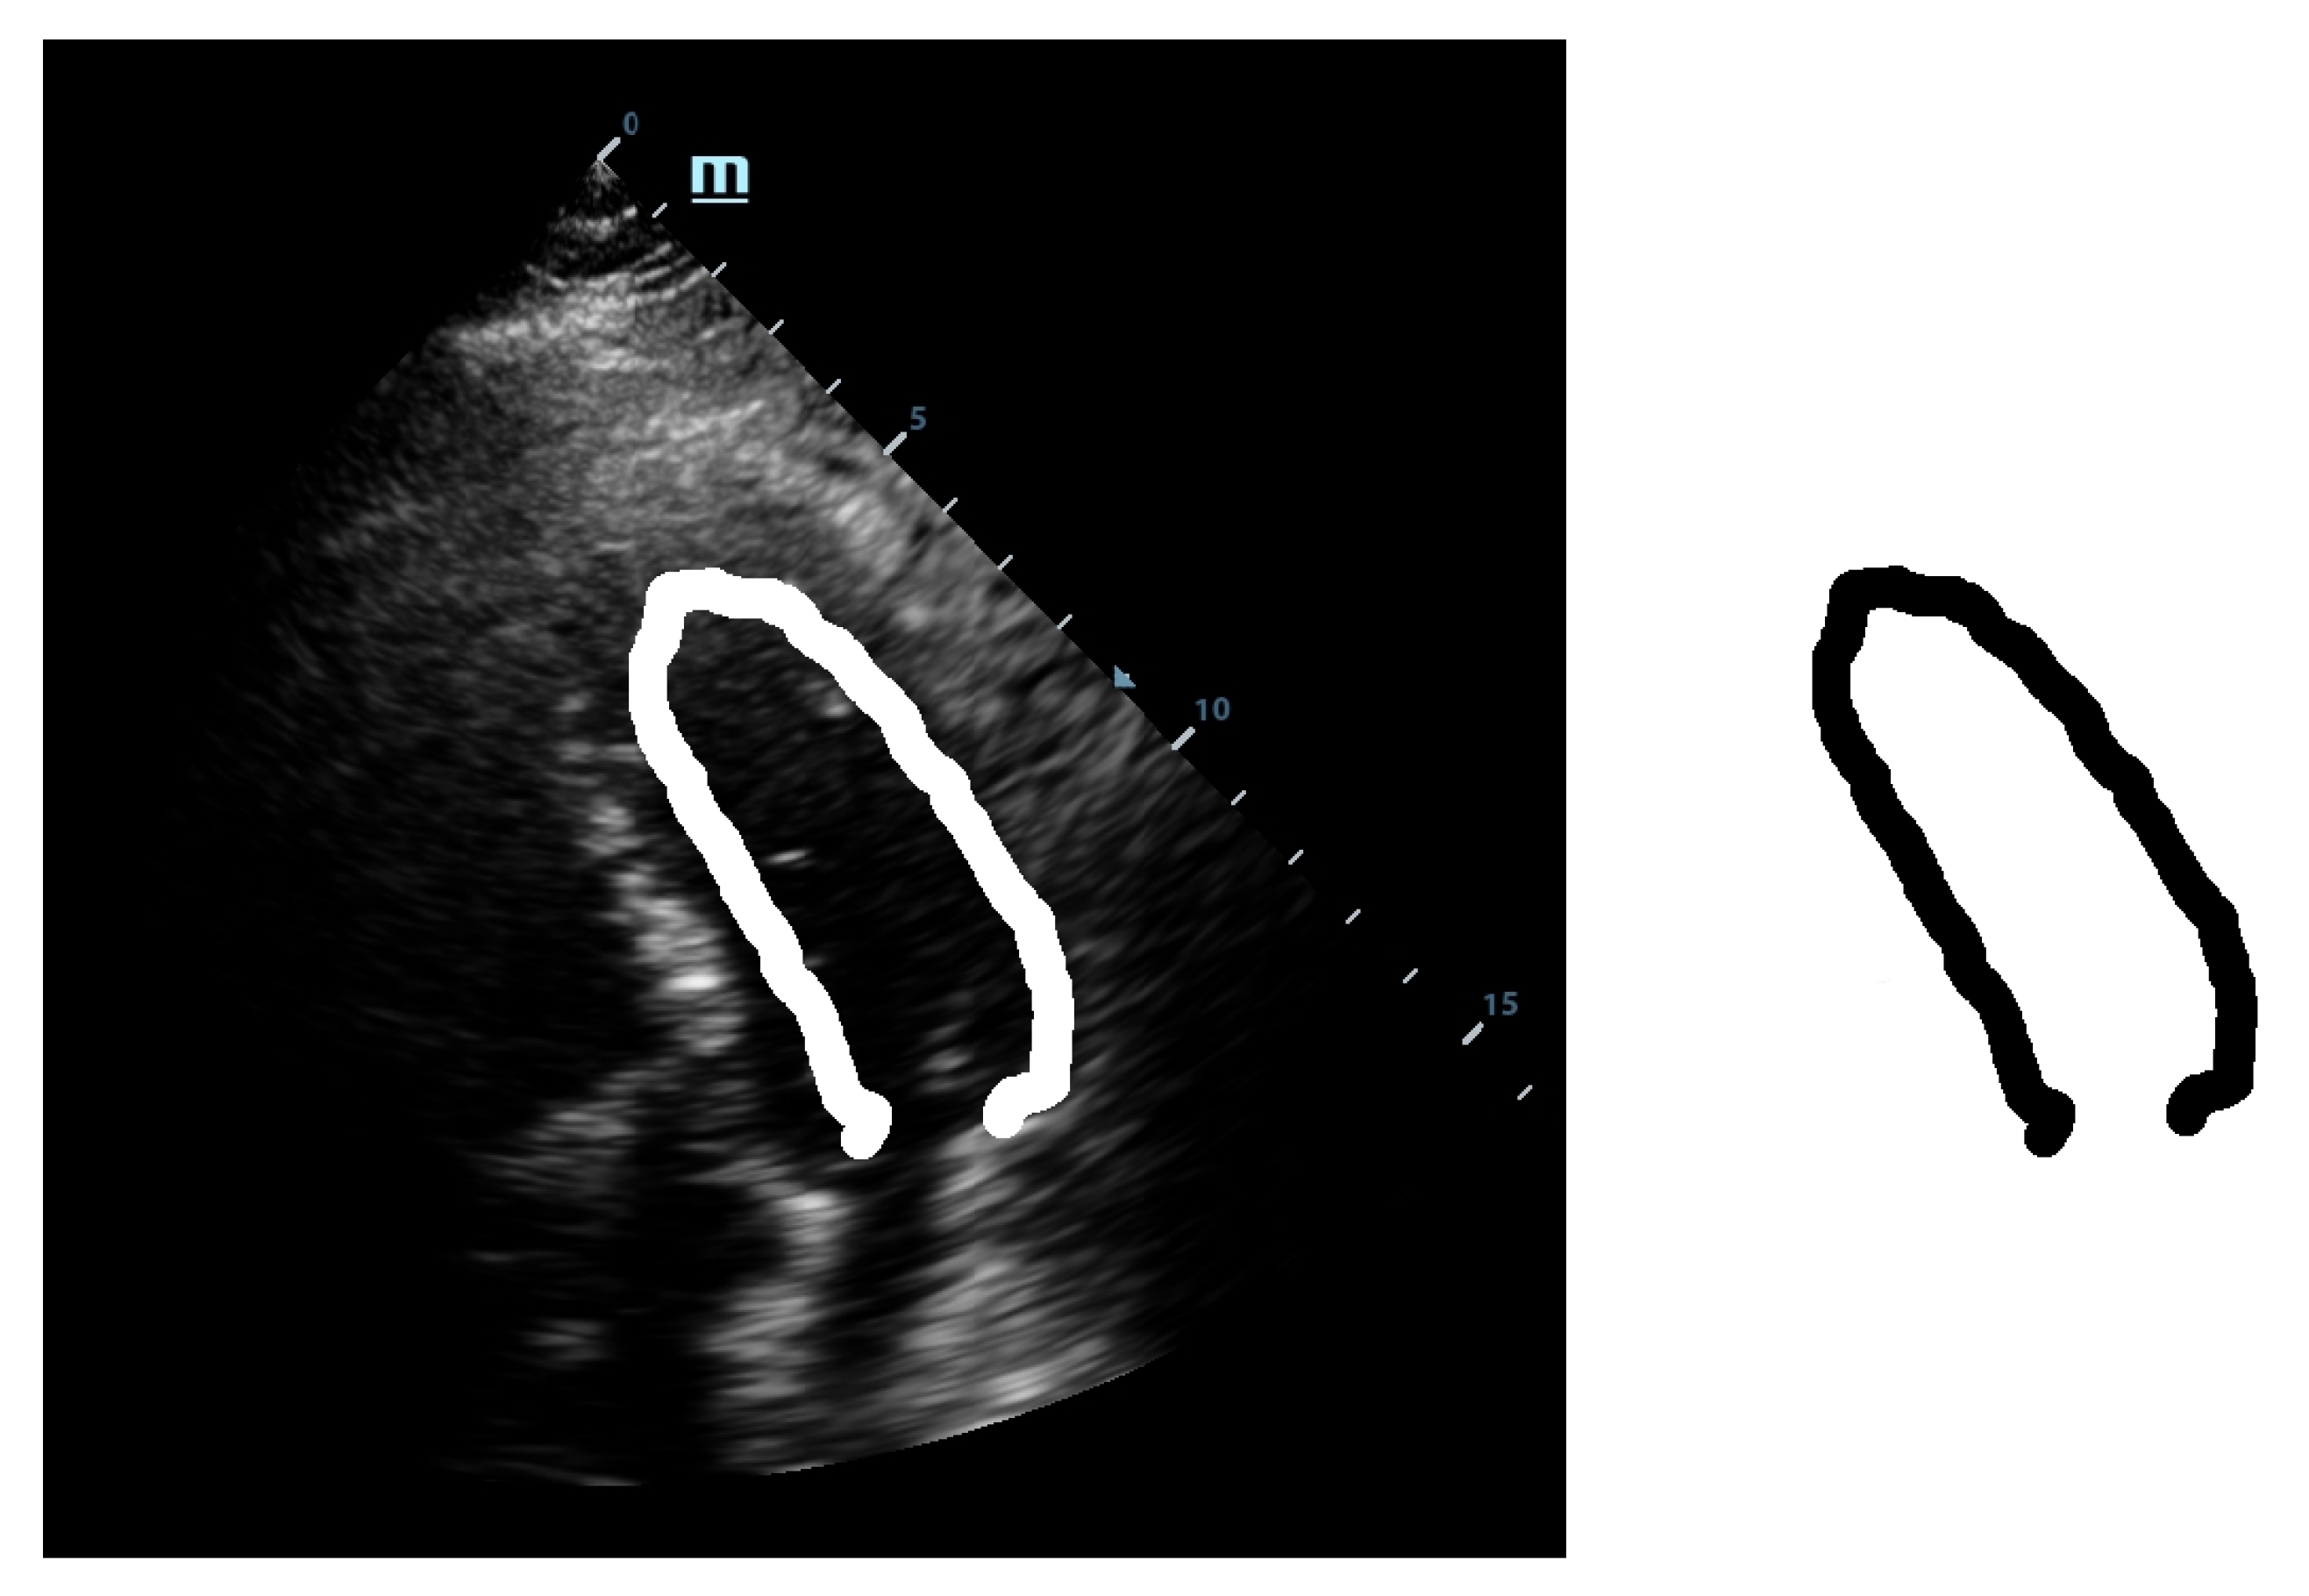

Simultaneously, by following the second path, we decided to also make also the template deformable, not only its application to the Hough transform. Therefore, we used the septal wall of the LV as guidance because this side has a higher visibility as it is not usually covered by other anatomical structures such as lungs or bones when observed echographically. To obtain a thinner line, the deformation was made within the original template. This way we managed to obtain the refined deformable template, as shown in Figure 4.

This template was then used as the guidance template. The medial wall was found and initially estimated. Afterwards, by applying the Hough transform, the deformation within the thick guidance template line was performed such that the delimitation of the lateral wall of the LV was obtained as accurately as possible while the rest of the template was thin because its primary use was for orientation purposes inside the echocardiographic image. The guidance template is suitable to adapt and localize within the ROI area of the left ventricle by making use of its visible anatomical features. This is needed also because the algorithm is adaptable to the phases of the heart and a fixed template would have not been able to recognize the boundaries of the LV in a lively-automatic fashion.

Figure 4. Refined anisotropic template.